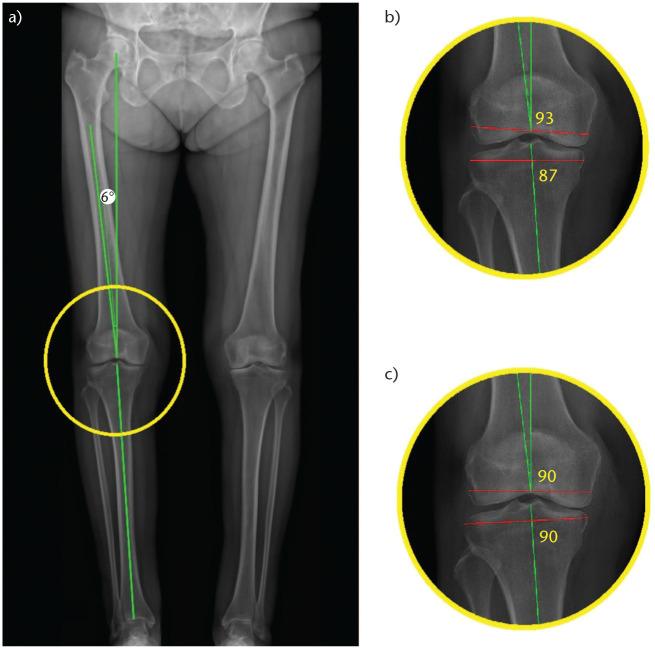

Although mechanical alignment (MA) has traditionally been considered the gold standard, the optimal alignment strategy for total knee arthroplasty (TKA) is still debated.Kinematic alignment (KA) aims to restore native alignment by respecting the three axes of rotation of the knee and thereby producing knee motion more akin to the native knee.Designer surgeon case series and case control studies have demonstrated excellent subjective and objective clinical outcomes as well as survivorship for KA TKA with up to 10 years follow up, but these results have not been reproduced in high-quality randomized clinical trials.Gait analyses have demonstrated differences in parameters such as knee adduction, extension and external rotation moments, the relevance of which needs further evaluation.Objective improvements in soft tissue balance using KA have not been shown to result in improvements in patient-reported outcomes measures.Technologies that permit accurate reproduction of implant positioning and objective measurement of soft tissue balance, such as robotic-assisted TKA and compartmental pressure sensors, may play an important role in improving our understanding of the optimum alignment strategy and implant position. Cite this article: 2020;5:486-497. DOI: 10.1302/2058-5241.5.190093.

尽管机械对线(MA)传统上一直被视为金标准,但全膝关节置换术(TKA)的最佳对线策略仍存在争议。运动学对线(KA)旨在通过尊重膝关节的三个旋转轴来恢复自然对线,从而使膝关节运动更接近自然膝关节。设计外科医生病例系列和病例对照研究表明,在长达10年的随访中,KA TKA具有出色的主观和客观临床结果以及生存率,但这些结果尚未在高质量的随机临床试验中得到重现。步态分析表明,诸如膝关节内收、伸展和外旋力矩等参数存在差异,其相关性需要进一步评估。尚未证明使用KA在软组织平衡方面的客观改善会导致患者报告的结局指标得到改善。能够精确再现植入物定位和客观测量软组织平衡的技术,如机器人辅助TKA和间隔压力传感器,可能在提高我们对最佳对线策略和植入物位置的理解方面发挥重要作用。引用本文:2020;5:486 - 497。DOI:10.1302/2058 - 5241.5.190093。